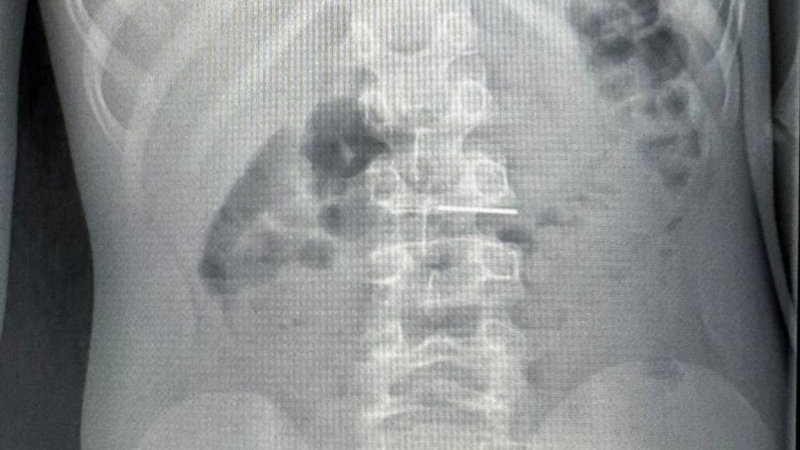

«Впервые в Иркутской области выполнили стентирование выводного отдела правого желудочка. Ювелирная процедура, каких в регионе никогда не проводилось. Хирургическое вмешательство проводилось с помощью высокотехнологичного ангиографа. Без разрезов, через прокол в несколько миллиметров», — написал Козлов в Telegram-канале.